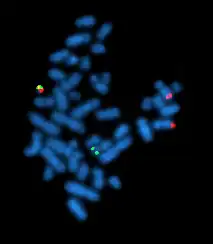

Флуоресце́нтная гибридиза́ция in situ, или метод FISH (англ. fluorescence in situ hybridization — FISH), — цитогенетический метод, который применяют для детекции и определения положения специфической последовательности ДНК на метафазных хромосомах или в интерфазных ядрах in situ. Кроме того, FISH используют для выявления специфических мРНК в образце ткани. В последнем случае метод FISH позволяет установить пространственно-временные особенности экспрессии генов в клетках и тканях.

Метод FISH используют в преимплантационной, пренатальной и постнатальной генетической диагностике[1], в диагностике онкологических заболеваний[2], в ретроспективной биологической дозиметрии[3].

Визуализацию связавшихся ДНК-зондов проводят при помощи флуоресцентного микроскопа. Интенсивность флуоресцентного сигнала зависит от многих факторов — эффективности мечения зондом, типа зонда и типа флуоресцентного красителя.